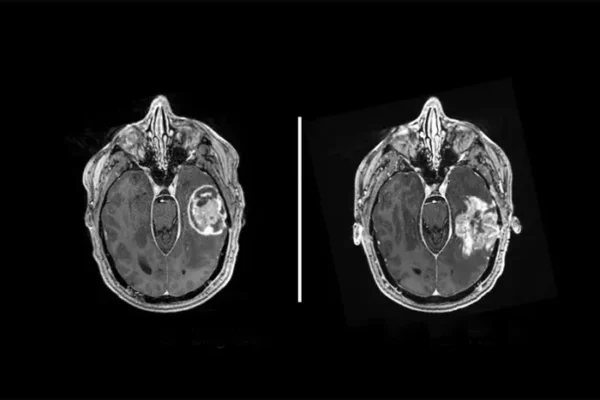

The challenge sounds straightforward until you peer through a microscope. Glioblastoma, the most common and lethal brain tumor, often masquerades as primary central nervous system lymphoma under standard staining techniques. Both cancers appear in the brain. Both show irregular cell patterns and necrotic tissue. Both demand immediate decisions. But they require opposite treatments. Glioblastoma needs surgical removal. PCNSL responds better to radiation and chemotherapy, making aggressive surgery not just unnecessary but potentially harmful.

During brain tumor operations, surgeons typically extract tissue samples for rapid microscopic evaluation. Pathologists freeze these samples in liquid nitrogen, slice them thin, and examine them within roughly 15 minutes. The freezing process distorts cellular features somewhat, creating a diagnostic challenge even under ideal circumstances. Based on this preliminary assessment, surgeons decide whether to continue removing tissue or halt the procedure.

The research team tested PICTURE’s performance specifically on frozen sections, the kind of samples that matter most for real-time surgical decisions. The system correctly identified cancers with accuracy ranging from 92.4 to 98.7 percent across different hospital sites, outperforming both human pathologists and other AI models on the most diagnostically challenging cases.

The system identifies specific tissue features that distinguish the two cancers. For glioblastoma, it focuses on dense tumor regions, microvascular proliferation, pseudopalisading necrosis, and infiltrating cells. For PCNSL, it highlights areas with high cellular density showing typical lymphoid morphology. Importantly, PICTURE marks regions with surgical artifacts, bleeding, or ambiguous features as low-confidence areas, preventing overconfident misdiagnosis.